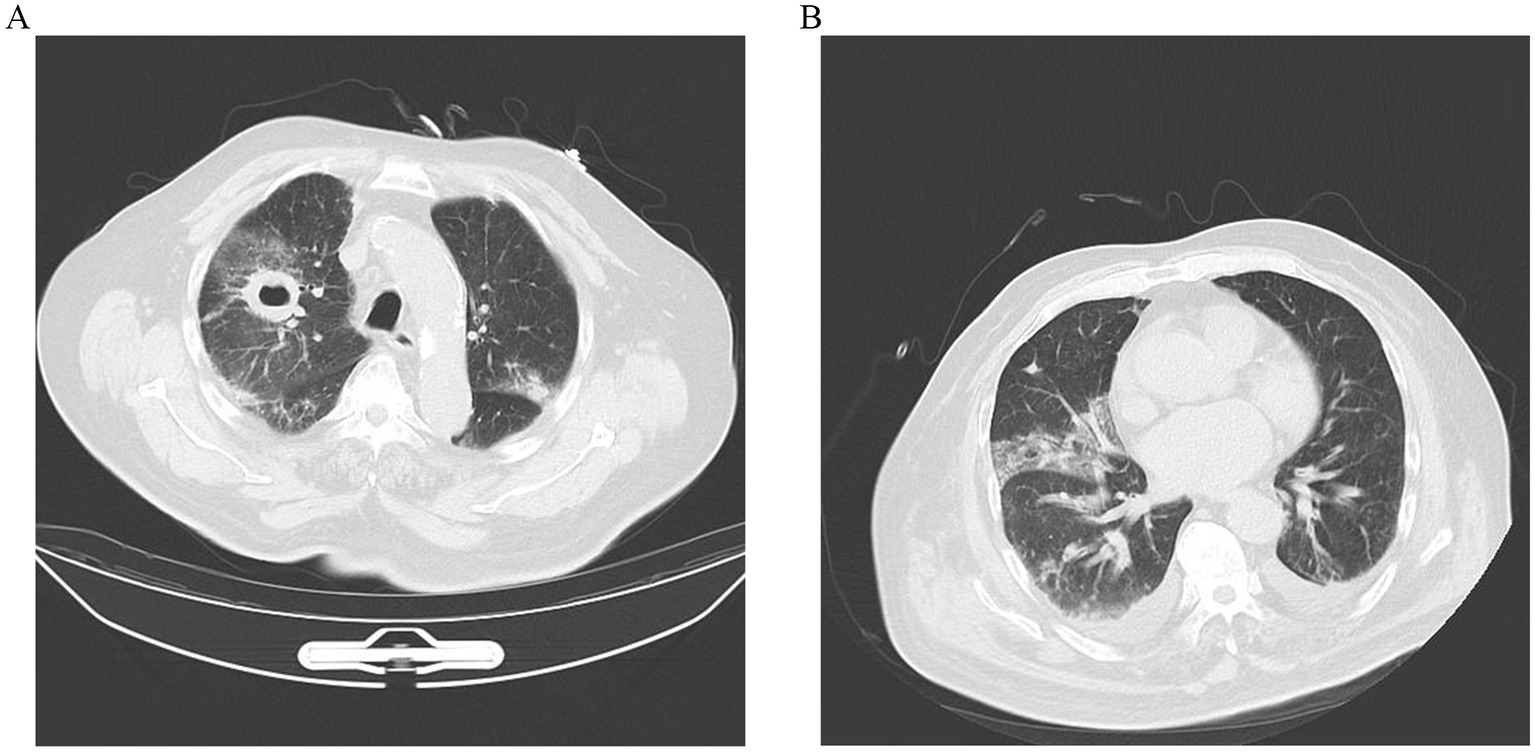

Two days later, despite being hemodynamically stable, the patient continued to be feverish with hemoptysis. Computed tomography (CT) scan of the chest indicated that lungs appeared inflammation, including a thick-walled cavity in the upper lobe of the right lung, an air sac cavity in the middle lobe of the right lung, and arteriosclerosis (Figure 1A).

Figure 1. (A) CT scan image of upper lobes of the lungs demonstrating bilateral pulmonary infection, with cavitation (about 32 × 40 mm) in the upper lobe of the right lung, and an air sac cavity in the middle lobe of the right lung. (B) After 10 days of antifungal treatment, chest CT showed a decrease in lung inflammation and a diminution of cavitation (about 29 × 21 mm) in the upper lobe of the right lung.

With the diagnosis of PM caused by Rhizopus microsporus, he was administered a high dosage of liposomal amphotericin B (10 mg/kg/d IV) with monitoring of renal functions and electrolytes. In addition, the patient was also treated with oseltamivir to fight the virus. However, after 5 days of antifungal therapy, the treatment was discontinued due to persistent severe hypokalemia, which was difficult to correct. Itraconazole (0.3 g/quaque die 1 day) was then initiated on day 5, accompanied by symptomatic supportive treatment for hypertension. After 10 days of antifungal therapy, repeated thoracic CT scan (Figure 1B) revealed the cavities in the lungs were significantly reduced in size, while the pleural effusion was slightly increased. But the WBC, CRP, and PCT levels remained elevated, and multiple plaques were found in the arteries of the left lower extremity. Furthermore, he remained afebrile with breathlessness. His sputum cultures showed Acinetobacter baumannii infection. The patient was added to intravenous meropenem (1 g/quaque die 12 h) for anti-infection treatment. Unfortunately, his symptoms of the infection did not improve and the disease progressed rapidly after 22 days of admission. He and his family decided to give up further treatment with progressive worsening of shortness of breath. The patient’s blood oxygen saturation was low at discharge, maintained at about 75–85% under oxygen inhalation. The patient died soon after discharge during the subsequent follow-up.